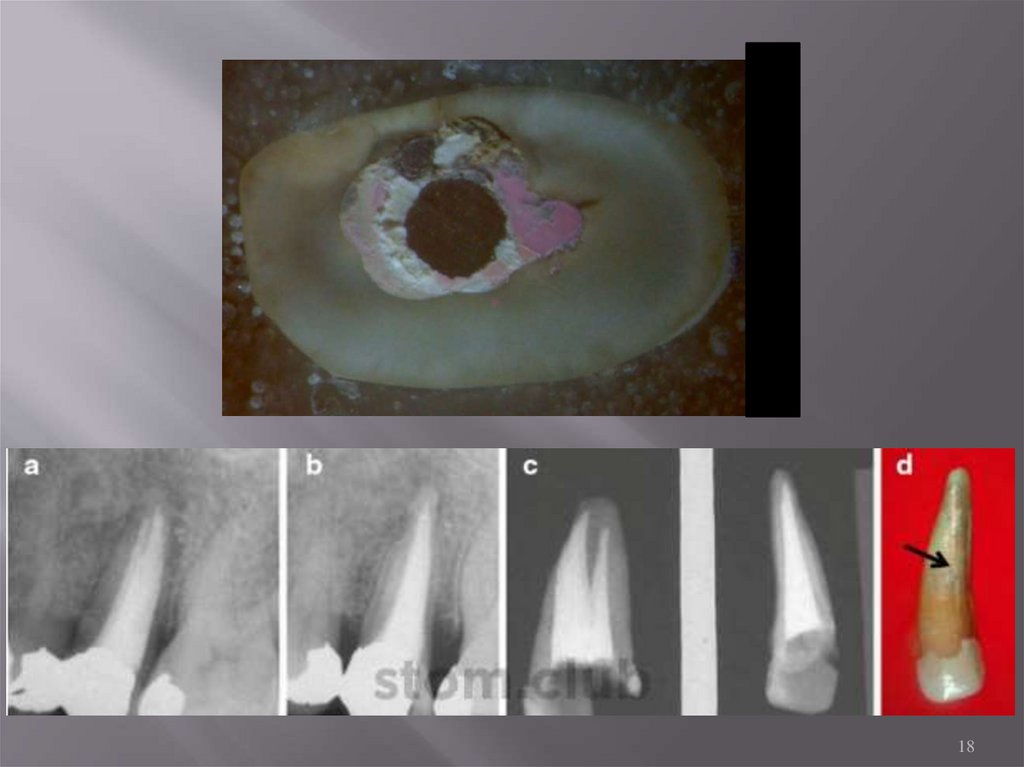

Фото: Андрей Дмитров

18